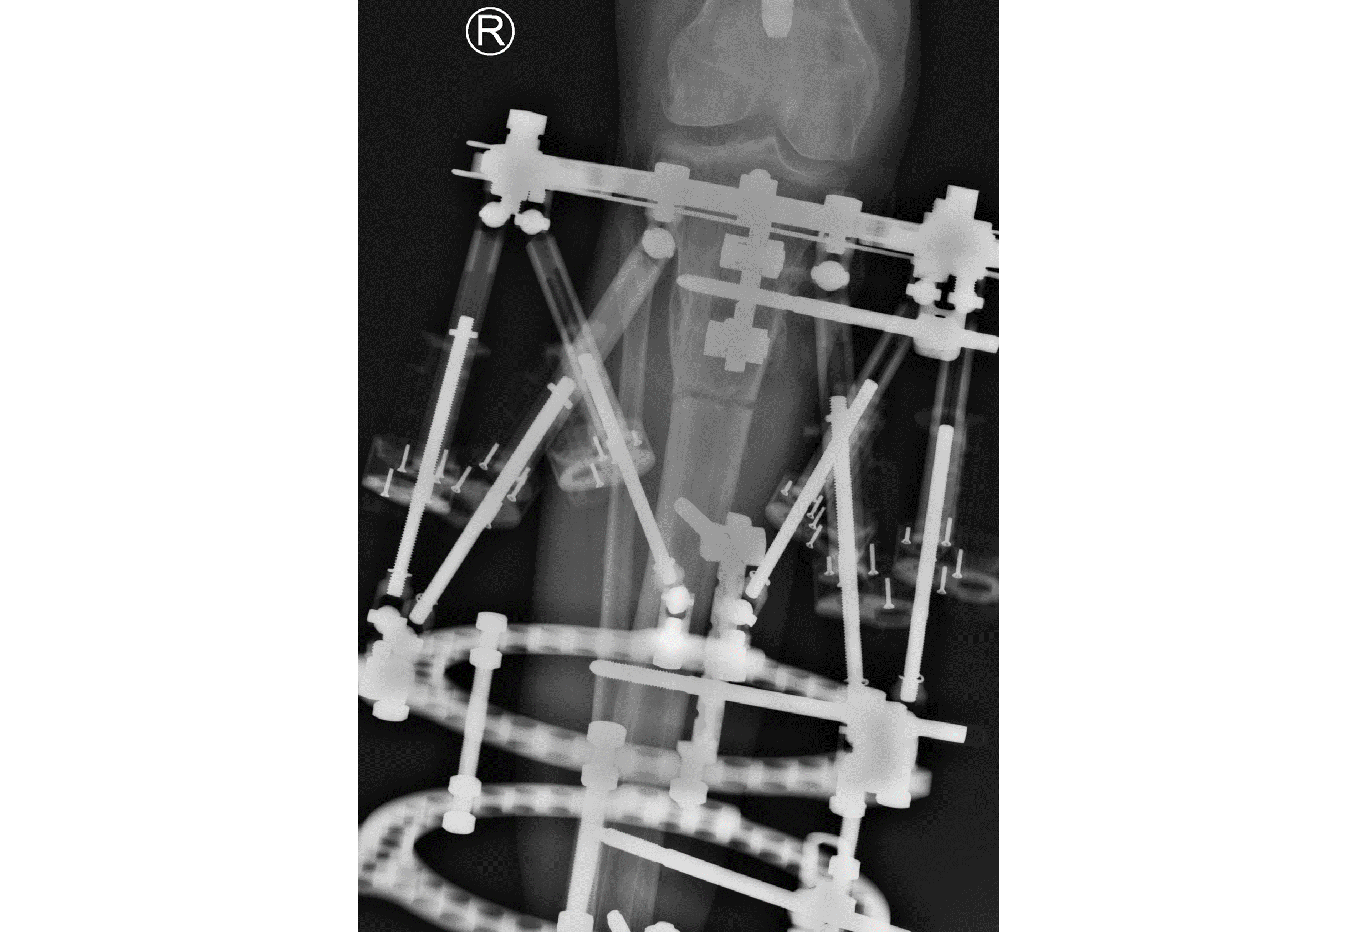

The tibial deformity was planned to be managed with a MAXFRAME AUTOSTRUT™.

The multiaxial correction system MAXFRAME™ has now firmly established itself as an integral part in the treatment of any bone deformity, be it posttraumatic, infectious, or congenital in origin. The implementation of new hardware components, such as the previously presented linear struts, have again increased the versatility and stability, and made the application simpler. The temporary use of the polyaxial struts is particularly helpful in the case of a strut change, as they guarantee high stability while performing a strut change and are easy to install (Fig 2).

The new software version addresses and integrates the innovative new hardware components MAXFRAME AUTOSTRUT. It enables full automation of strut adjustments through motorized struts and provides a solution to various drawbacks of a traditional hexapod external ring-fixation treatment.